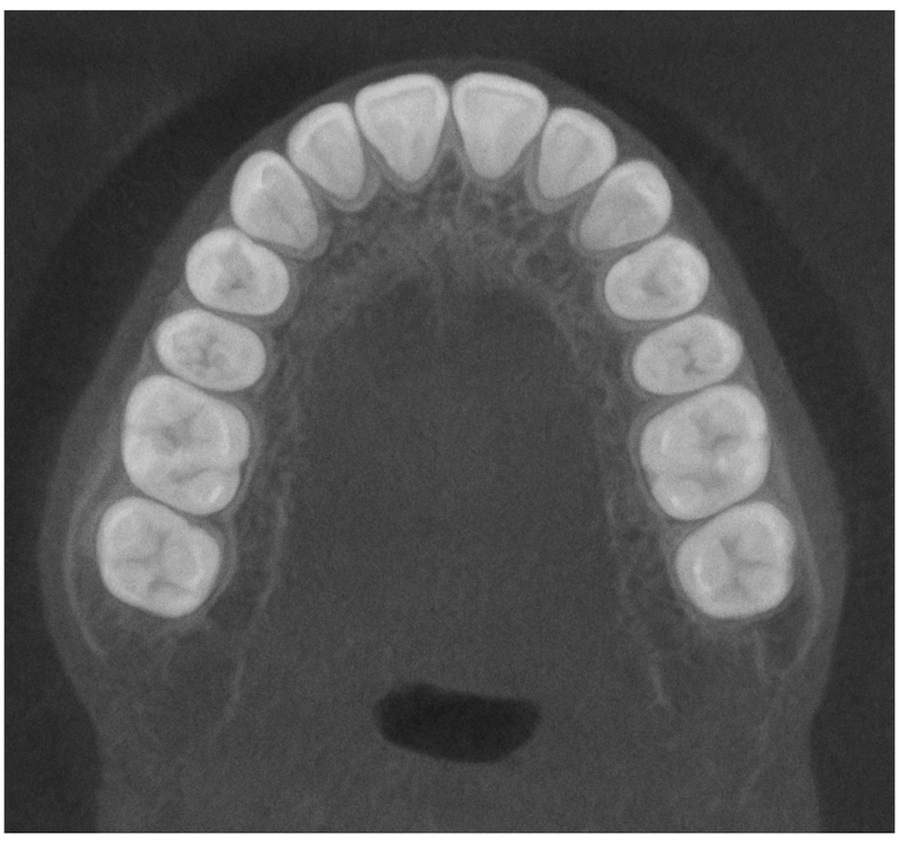

The Panoramic OP 3D LX is an advanced dental imaging system designed to provide a complete, high-resolution view of your entire mouth in a single image. This technology captures your teeth, jawbones, and surrounding structures with remarkable clarity, helping dentists identify issues such as cavities, infections, bone loss, and impacted teeth. Its quick, comfortable process makes it an excellent tool for routine check-ups, pre-treatment evaluations, and surgical planning. The OP 3D LX minimizes patient radiation exposure while maximizing diagnostic accuracy, ensuring a safe and effective experience for every patient.